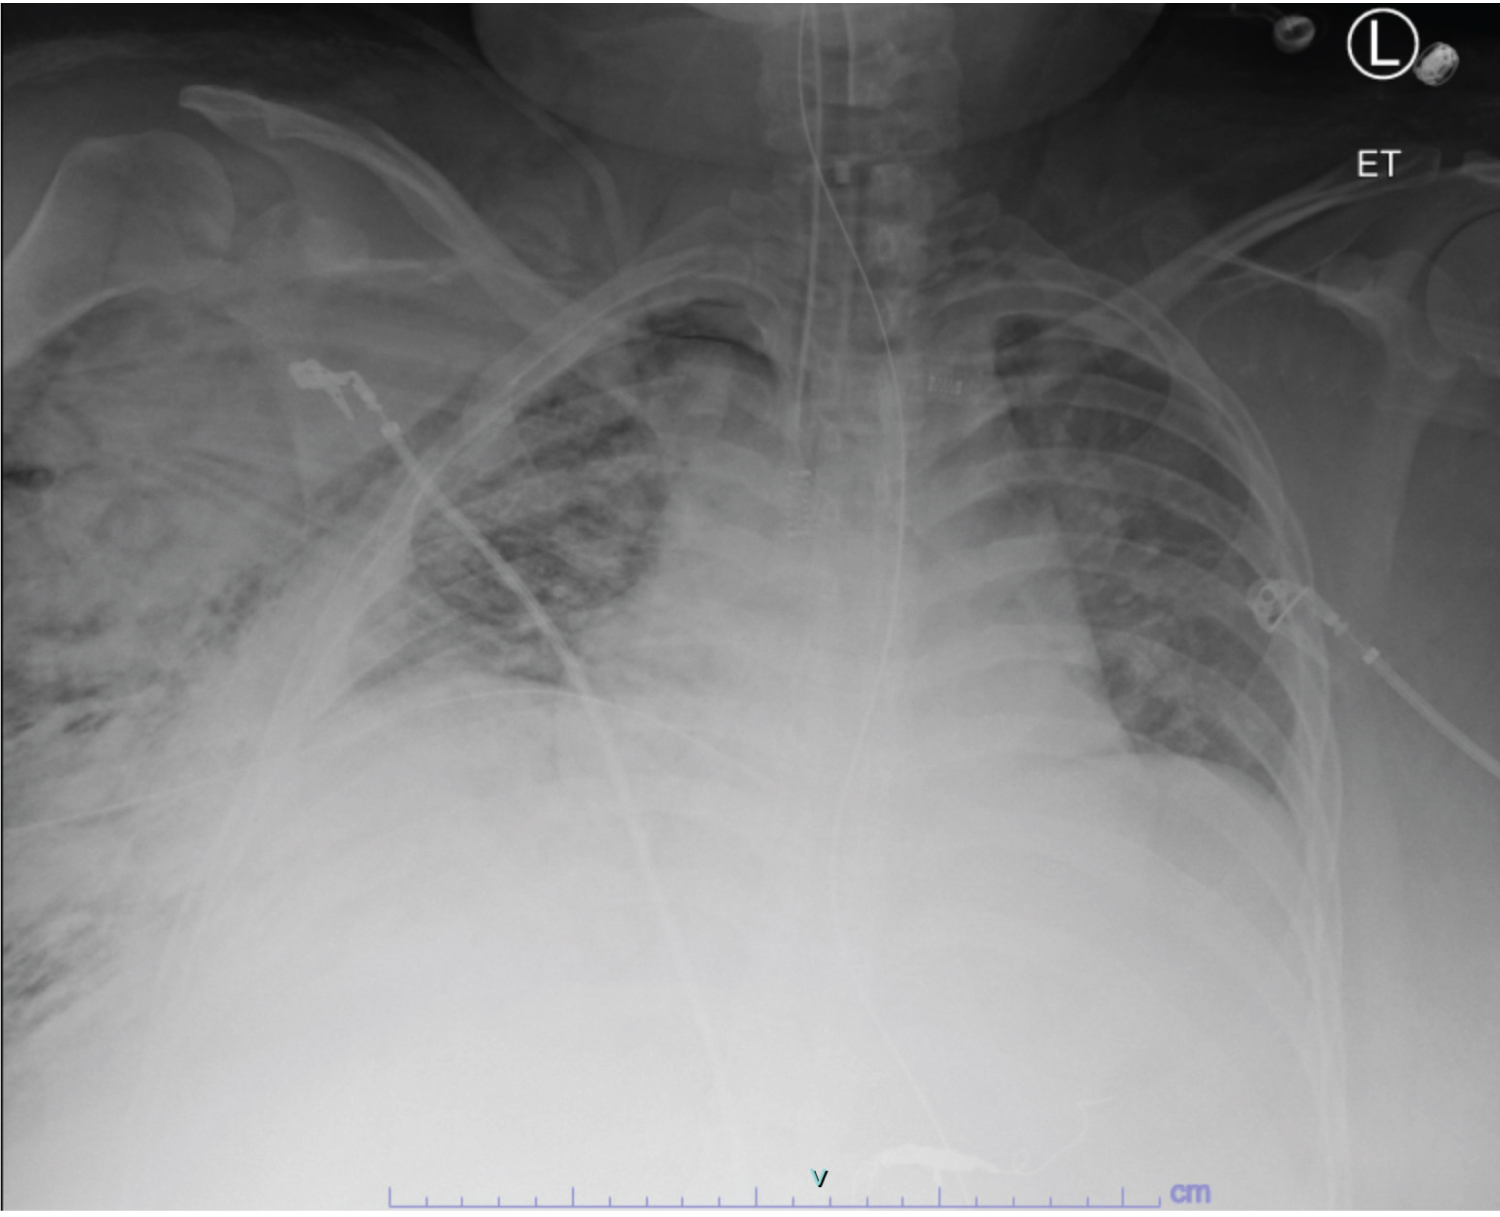

A 45-year-old female with no known past medical history presented to the trauma unit as an unrestrained passenger in a motor vehicle accident. On arrival, her GCS was 8 and she was intubated. Focused Assessment with Sonography for Trauma (FAST) exam was negative, but initial chest imaging (Figure 1A and Figure 1B) revealed right-sided fractures of the first through seventh ribs, a fracture of the left first rib with bilateral consolidations, and a small right-sided hemopneumothorax. Further imaging showed hepatic vascular injury, Grade 2 splenic injury, Grade 5 renal injury, and a non-displaced fracture of the right L5 transverse process.

Figure 1a: Axial CT with contrast shows right-sided pneumothorax (white arrow) and bilateral layering consolidations (red arrows).

Figure 1b: Portable chest X-ray shows fractures of the right second through fourth ribs (white arrows). Corresponding CT (Figure 1A) confirmed fractures of the right first through seventh ribs, left first rib, and right L5 transverse process.